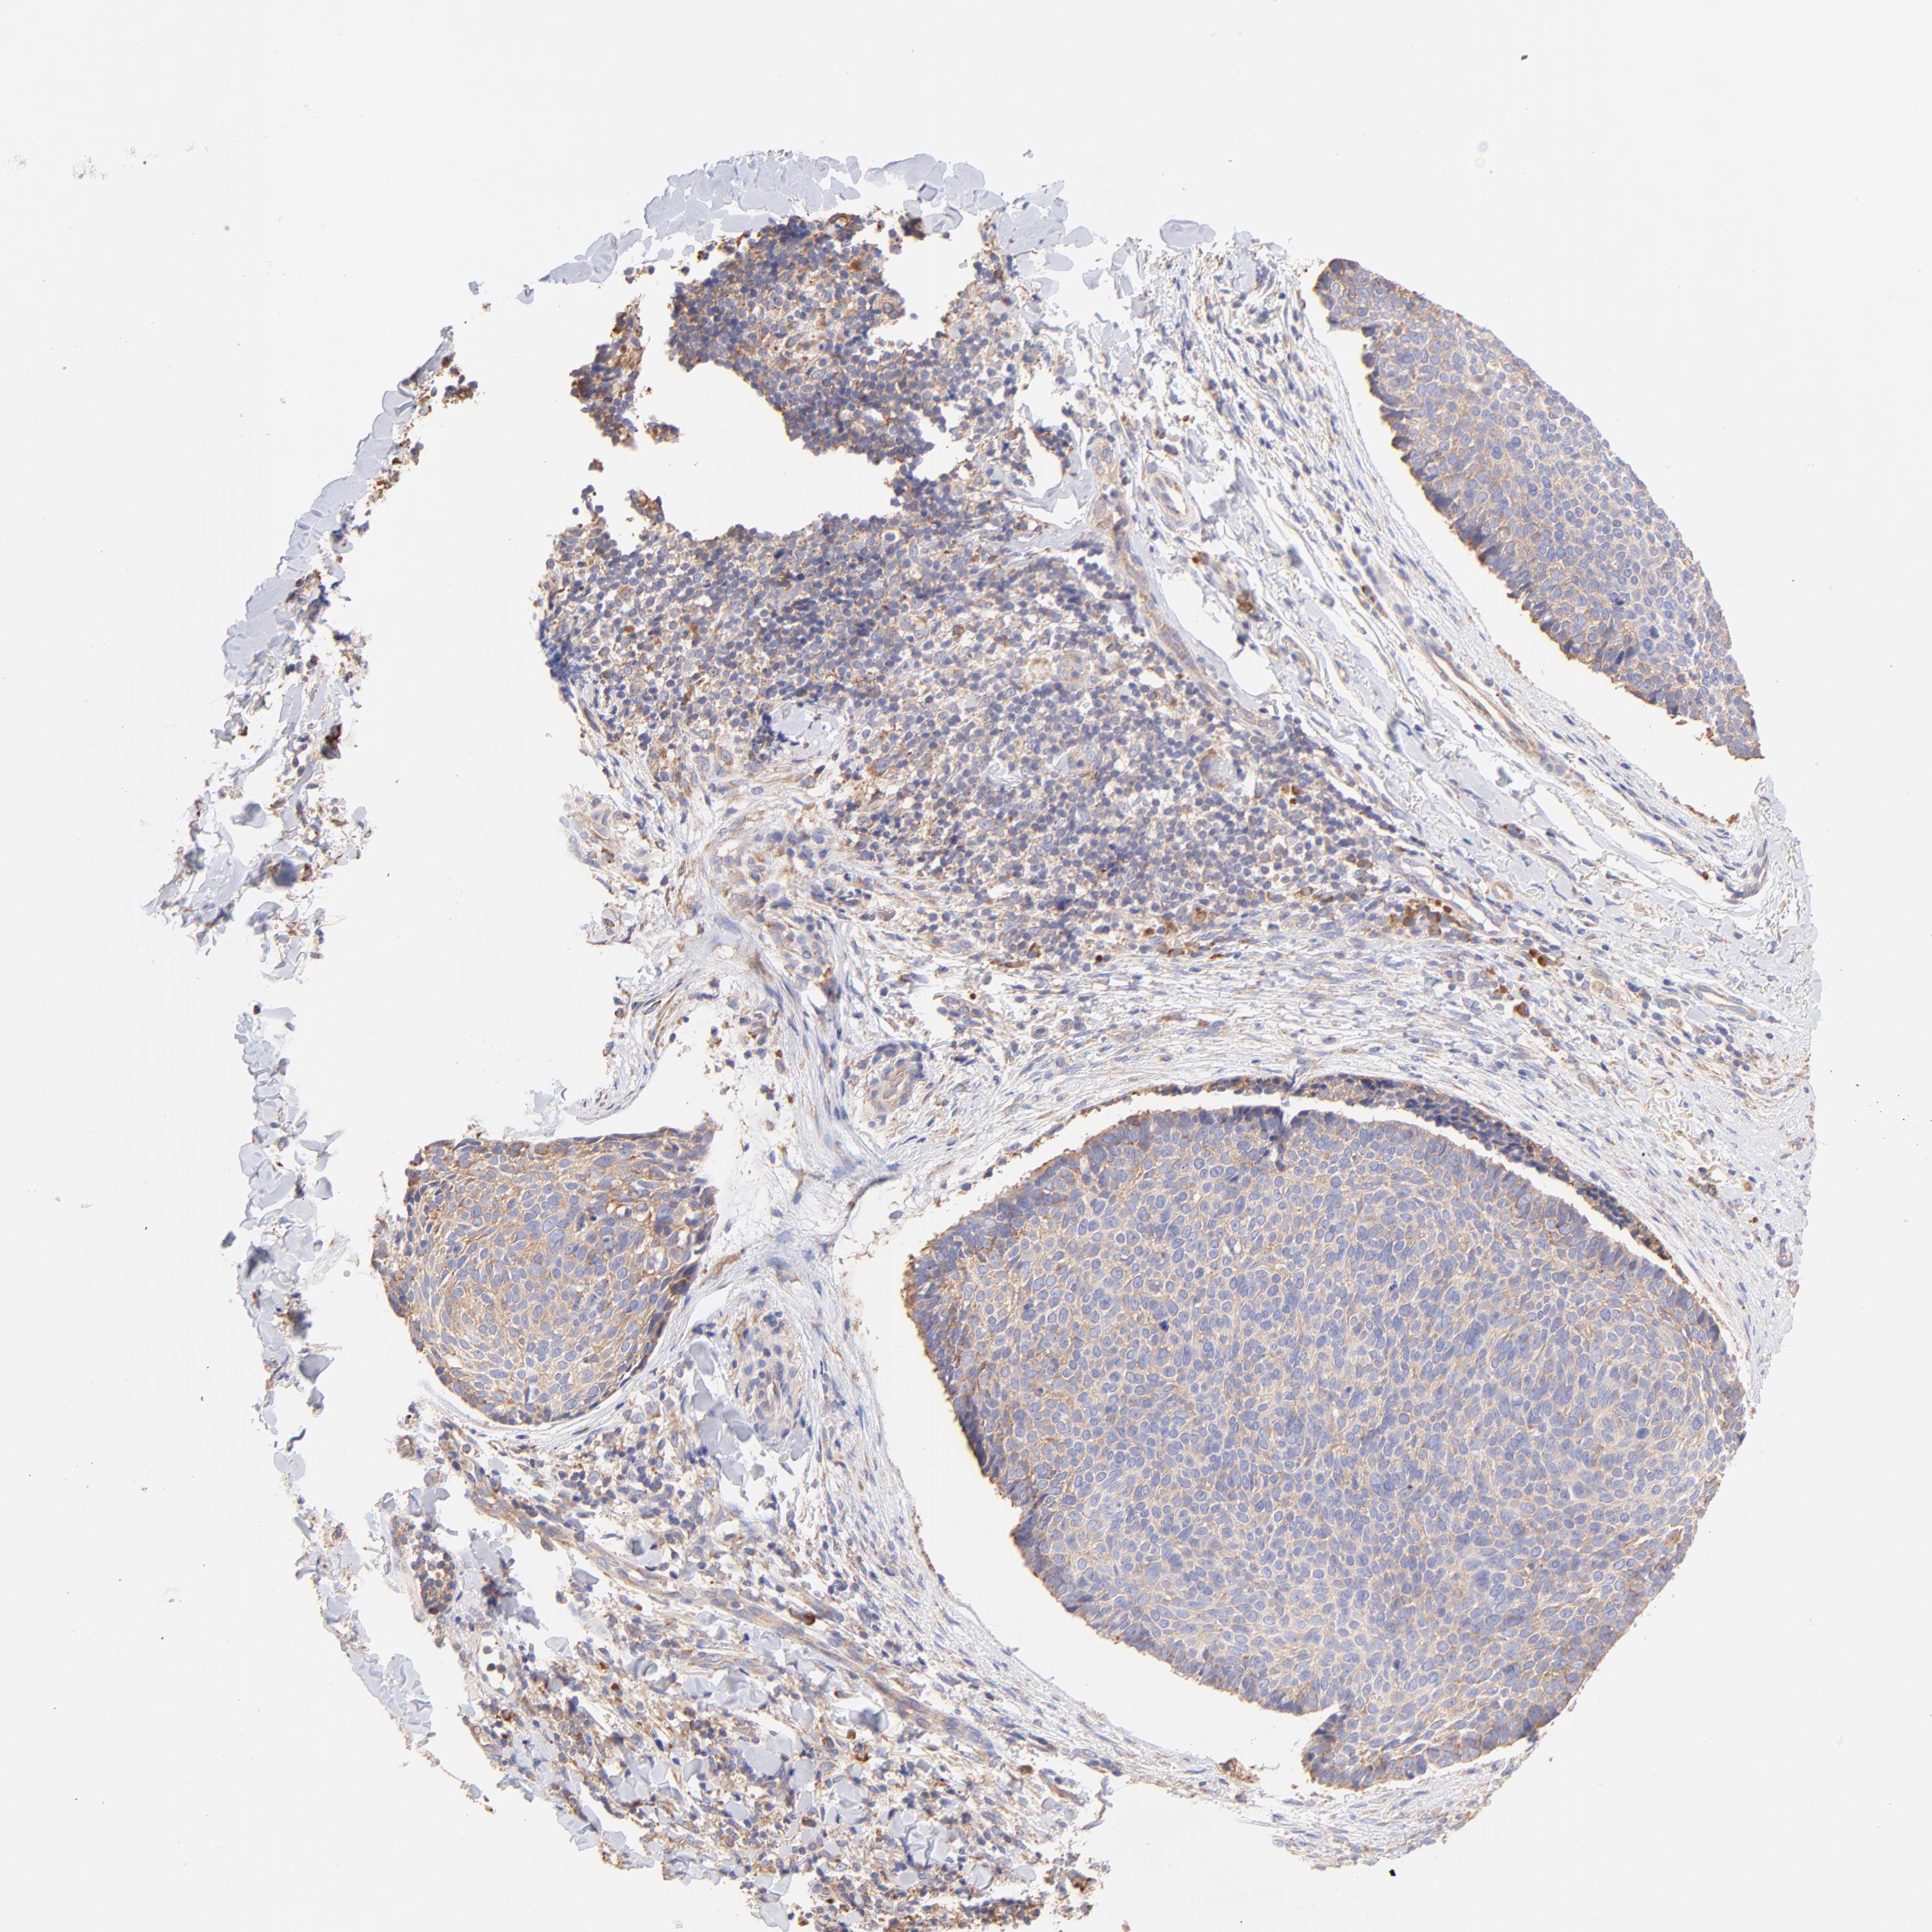

SKIN CANCER - Protein expressioni

A mouse-over function shows sample information and annotation data. Click on an image to view it in a full screen mode. Samples can be filtered based on level of antibody staining by selecting one or several of the following categories: high, medium, low and not detected. The assay and annotation is described here.

Antibody stainingi

Antibody staining in the annotated cell types in the current human tissue is reported as not detected, low, medium, or high, based on conventional immunohistochemistry profiling in selected tissues. This score is based on the combination of the staining intensity and fraction of stained cells.

Each image is clickable and will lead to virtual microscopy that enables deeper exploration of all samples and also displays staining intensity scores, fraction scores and subcellular localization as well as patient and tissue information for each sample.

Antibody HPA002651

Staining

High

Medium

Low

Not detected

Intensity

Strong

Moderate

Weak

Negative

Quantity

>75%

75%-25%

<25%

None

Location

Nuclear

Cytoplasmic/membranous

Cytoplasmic/membranous,nuclear

Basal cell carcinoma